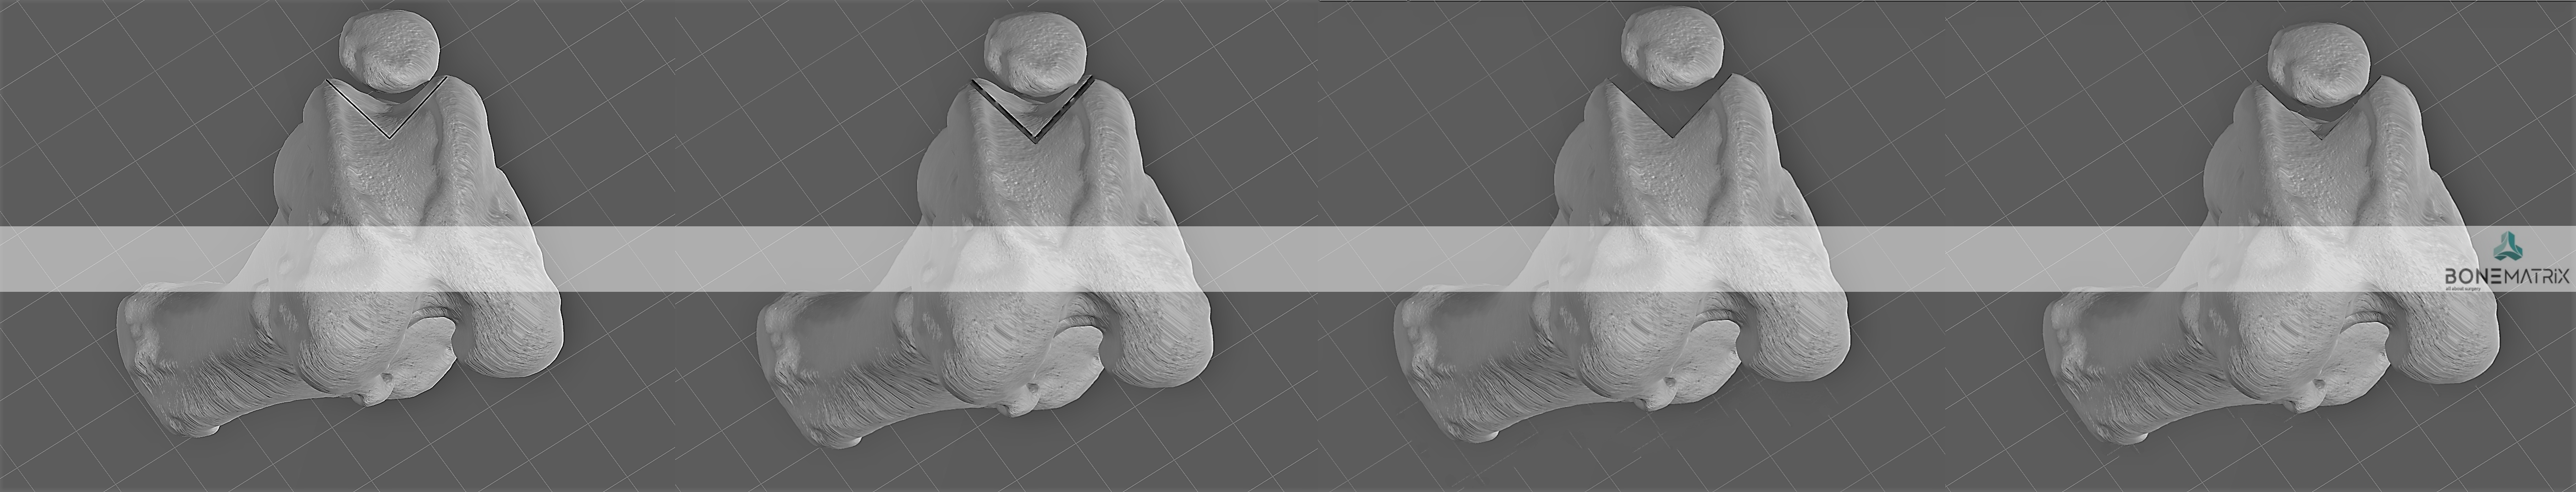

O que é a sulcoplastia?

A sulcoplastia consiste numa cirurgia onde são realizados dois cortes no sulco troclear (local onde desliza a patela durante o movimento do joelho) para permitir o aprofundamento deste sulco e recuperação da capacidade de delimitação do movimento da patela.

Qual a necessidade de realização deste procedimento?

A patologia de luxação de patela pode ser provocada por várias deformidades, um conjunto delas é categorizada como incompetência troclear.

A incompetência troclear surge quando a razão da patela não se manter no seu lugar anatómico se deve a alterações na conformação da tróclea. Esta alteração podem surgir desde uma idade muito jovem do animal, quando o paciente apresenta desde o início do seu crescimento um grau de luxação de patela muito elevado, o que faz com que esta passe a maior parte do tempo fora do sulco troclear. Nestes casos o sulco apresenta-se pouco profundo não apresentando capacidade de delimitar o movimento da patela.

As alterações podem também surgir em graus de patologia menos severos, onde existe um movimento constante da patela dentro e fora do sulco. A presença da patologia nestas condições faz com que, no movimento constante de saída da patela, exista um desgaste do osso no limite da tróclea para o lado em que ocorre a luxação, perdendo a capacidade de delimitar o percurso correto da rótula.

Em situações ligeiras, onde não existe dano cartilagíneo, apenas um defeito de conformação, poderá ser aplicada a sulcoplastia para aprofundamento deste sulco troclear, devolvendo assim competência ao sulco.

O que é o PGR?

O PGR (patellar groove replacement) é uma hemi-protese de joelho que corresponde apenas à parte do sulco troclear.

A cirurgia para colocação deste implante consiste na realização de um corte que elimina a estrutura original com alterações patológicas e posterior substituição pelo impante que apresenta as mesmas características que deveria ter um sulco normal.

Este implante é feito em titânio devido às suas características mecânicas que favorecem um movimento articular fluido e devido às suas características biocompatíveis.

Quando é necessária a colocação deste implante?

Em casos onde existam lesões cartilagíneas severas associadas ao sulco troclear (local onde a patela desliza durante o movimento do joelho) a colocação deste implante irá retirar a dor associada a este movimento.